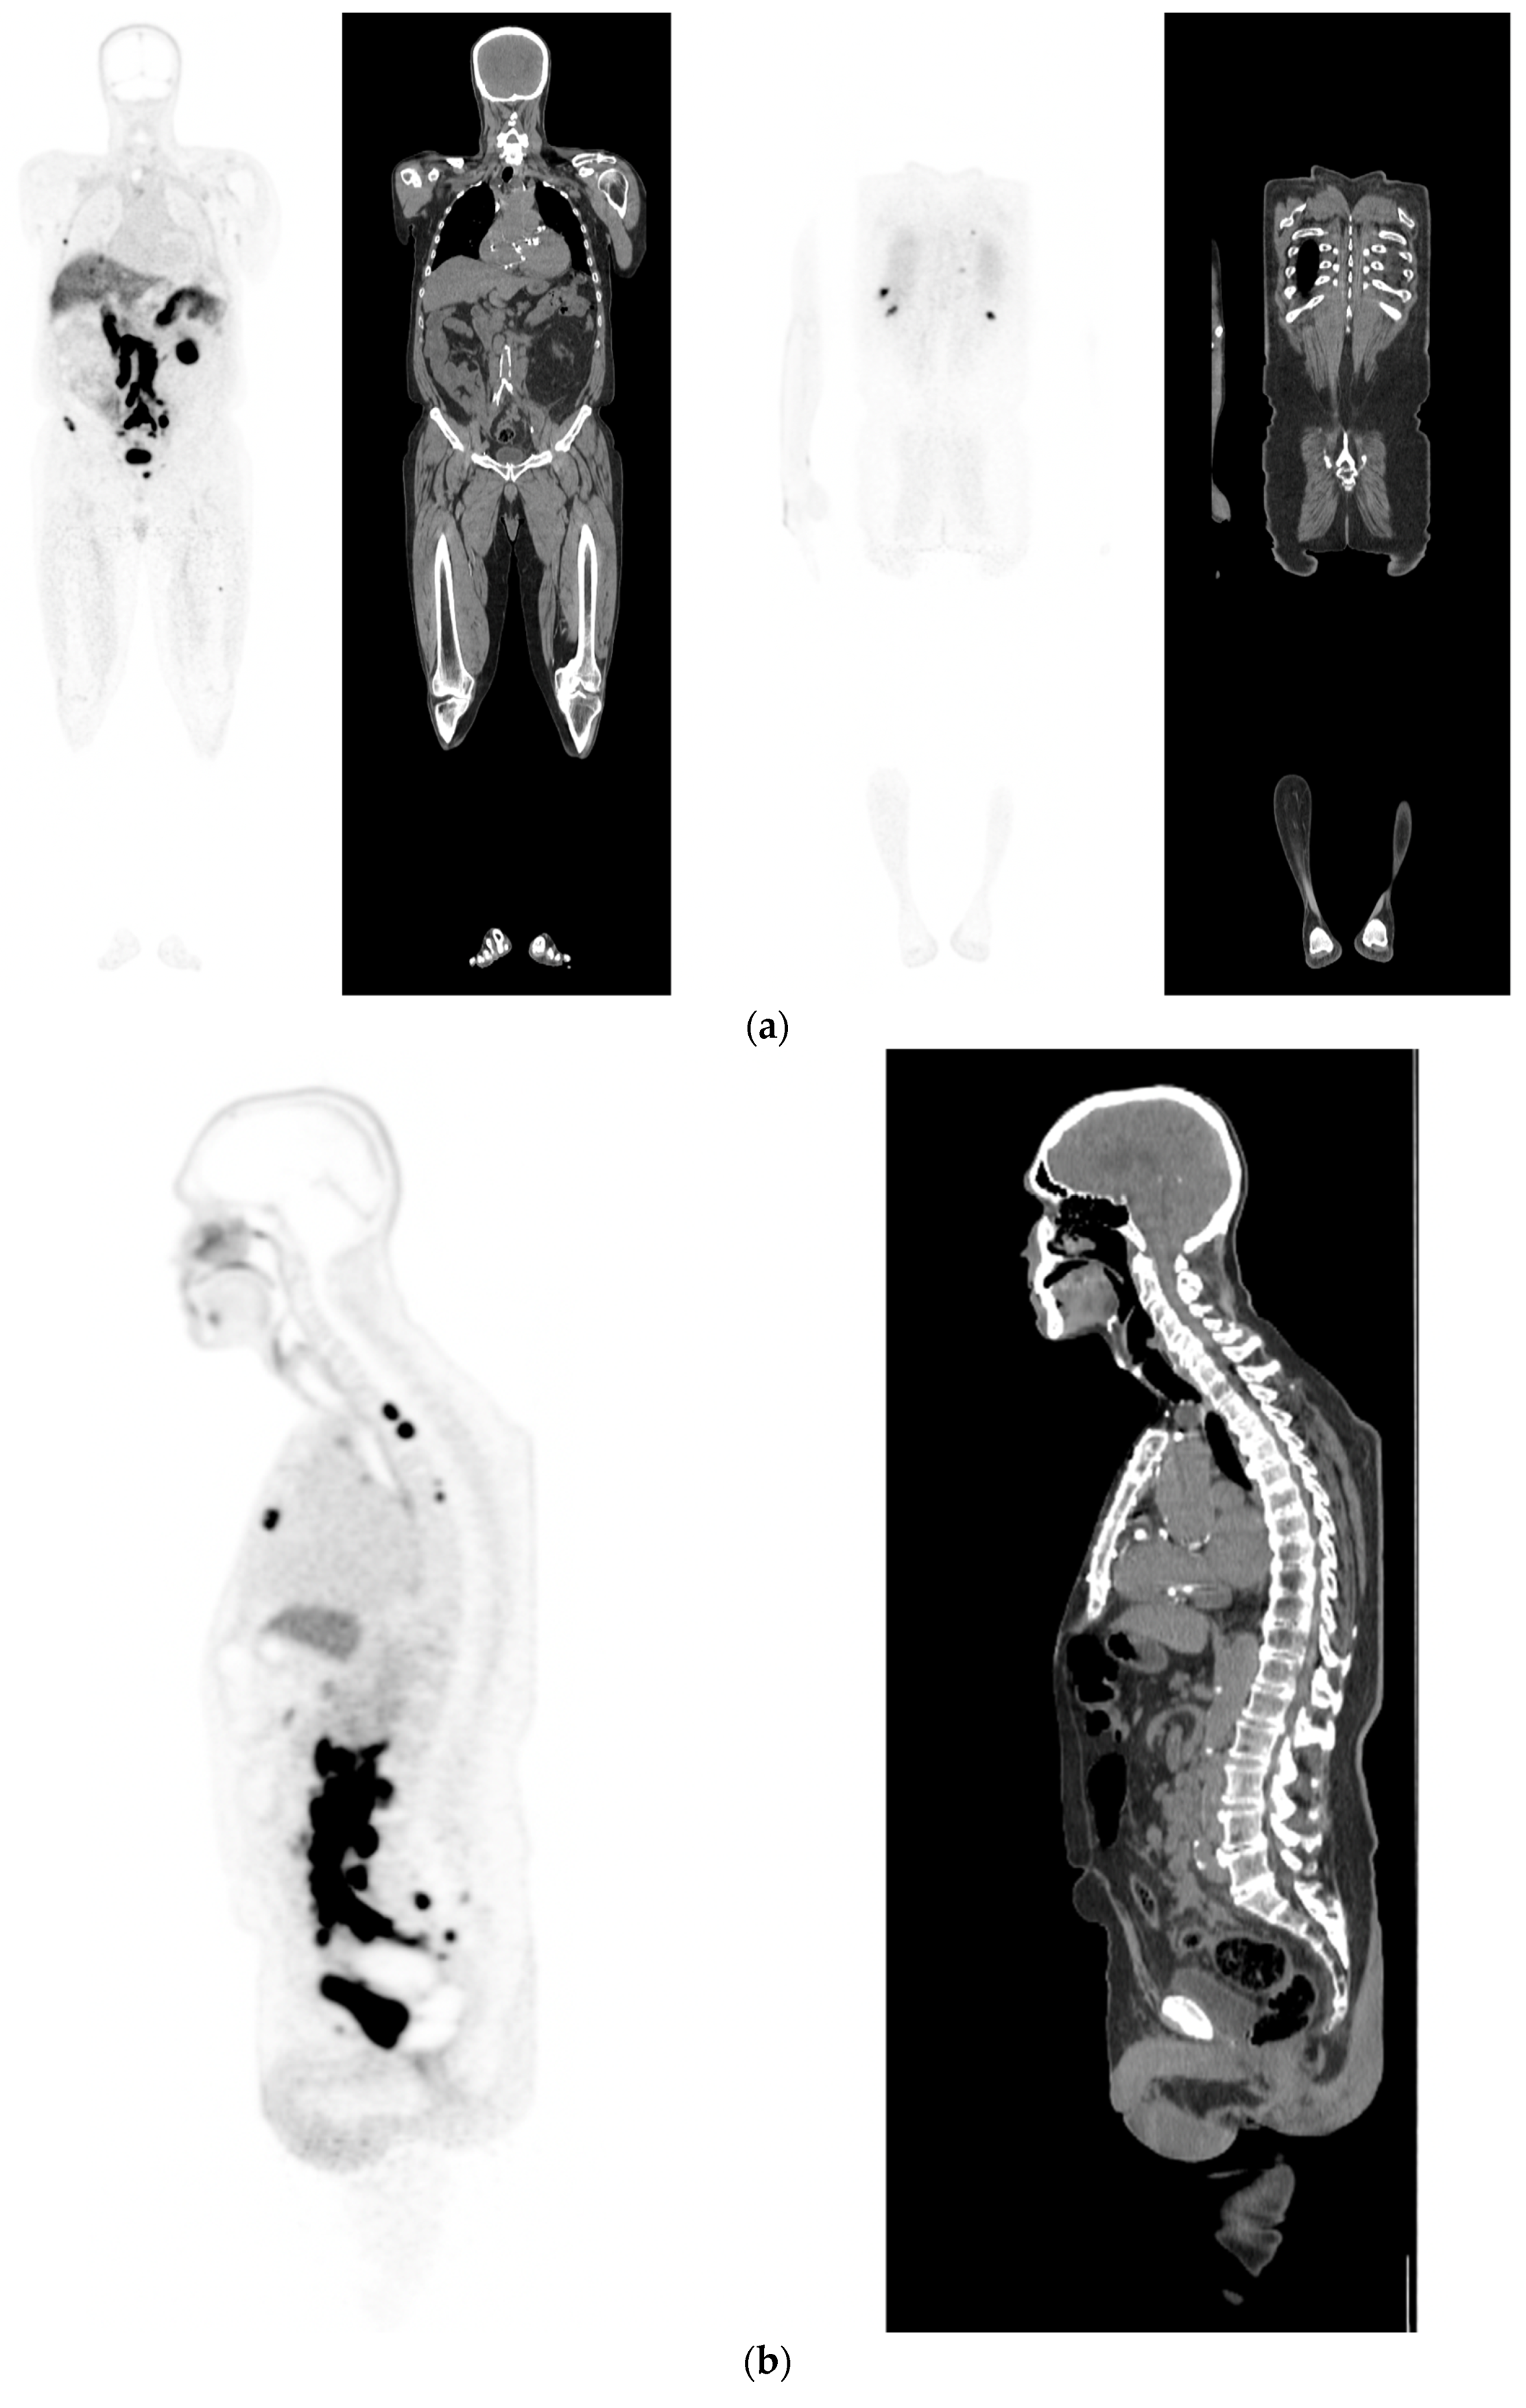

- Damjanovic, J.; Janssen, J.C.; Prasad, V.; Diederichs, G.; Walter, T.; Brenner, W.; Makowski, M.R. 68Ga-PSMA-PET/CT for the evaluation of liver metastases in patients with prostate cancer. Cancer Imaging 2019, 19, 37. [Google Scholar] [CrossRef]

- Damjanovic, J.; Janssen, J.C.; Furth, C.; Diederichs, G.; Walter, T.; Amthauer, H.; Makowski, M.R. 68Ga-PSMA-PET/CT for the evaluation of pulmonary metastases and opacities in patients with prostate cancer. Cancer Imaging 2018, 18, 20. [Google Scholar] [CrossRef]